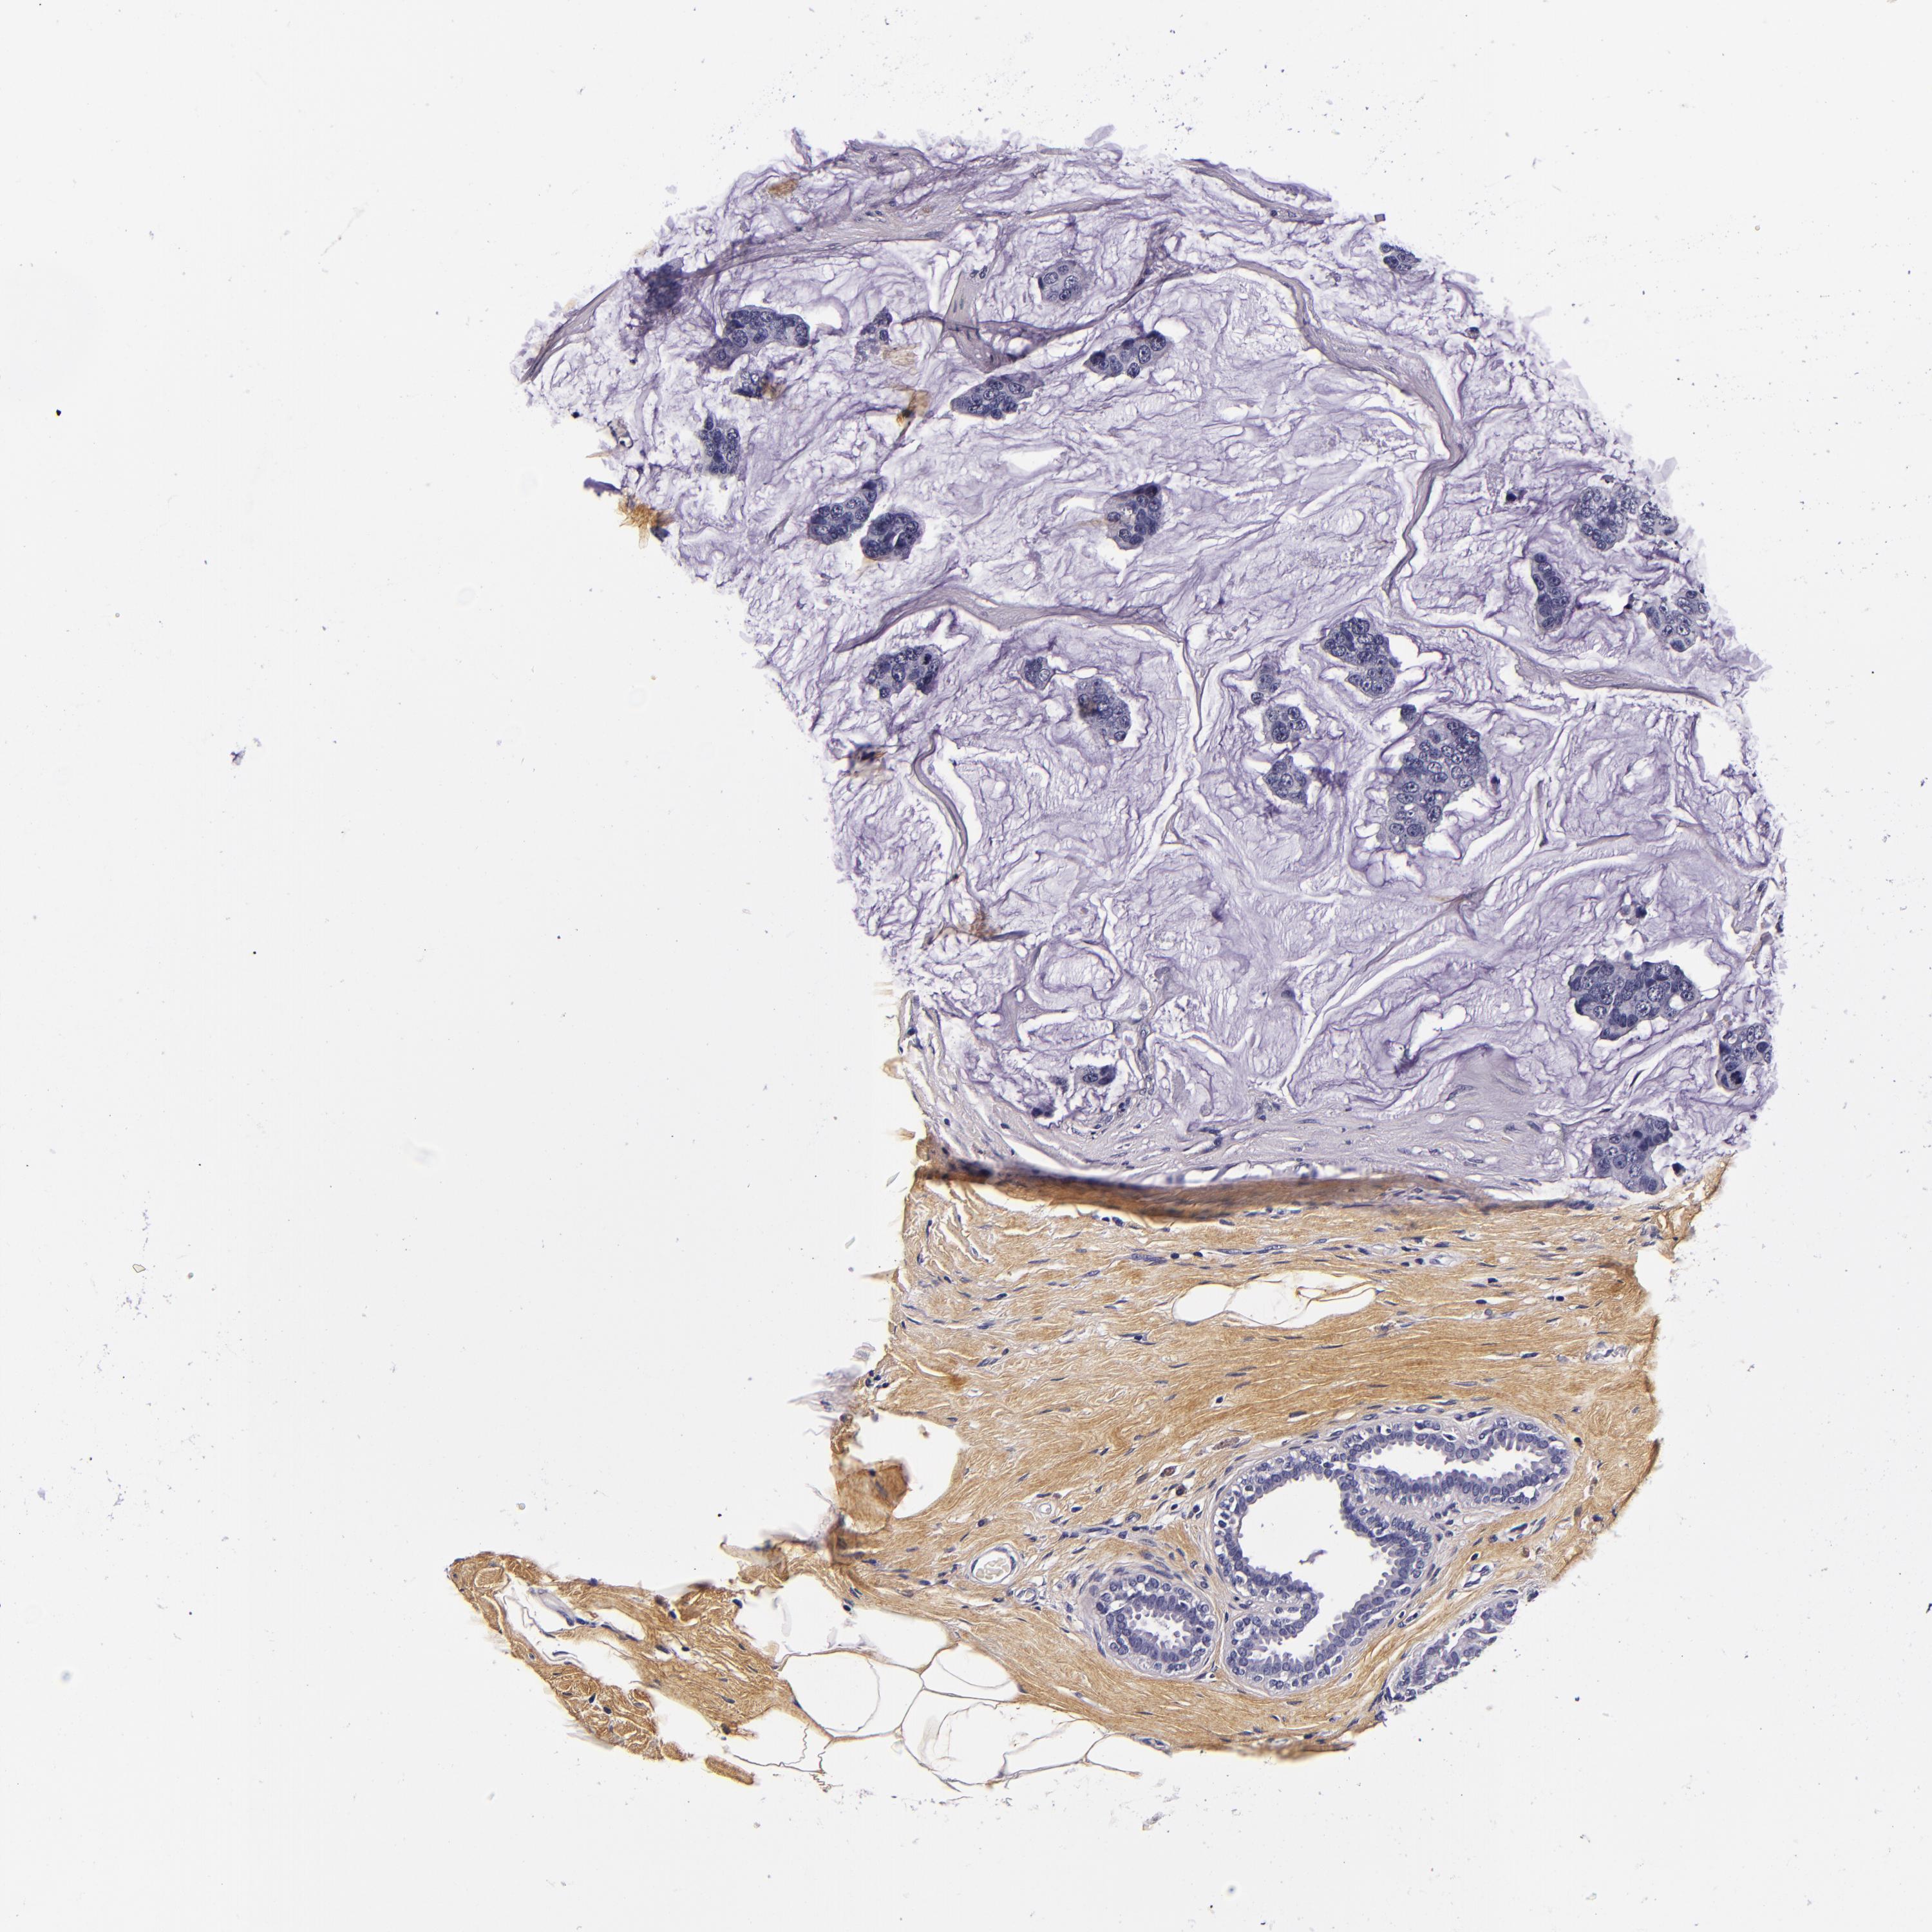

BRCA TCGA BRCA VALIDATION PROTEIN EXPRESSION

ANTIBODIES

AND

VALIDATION